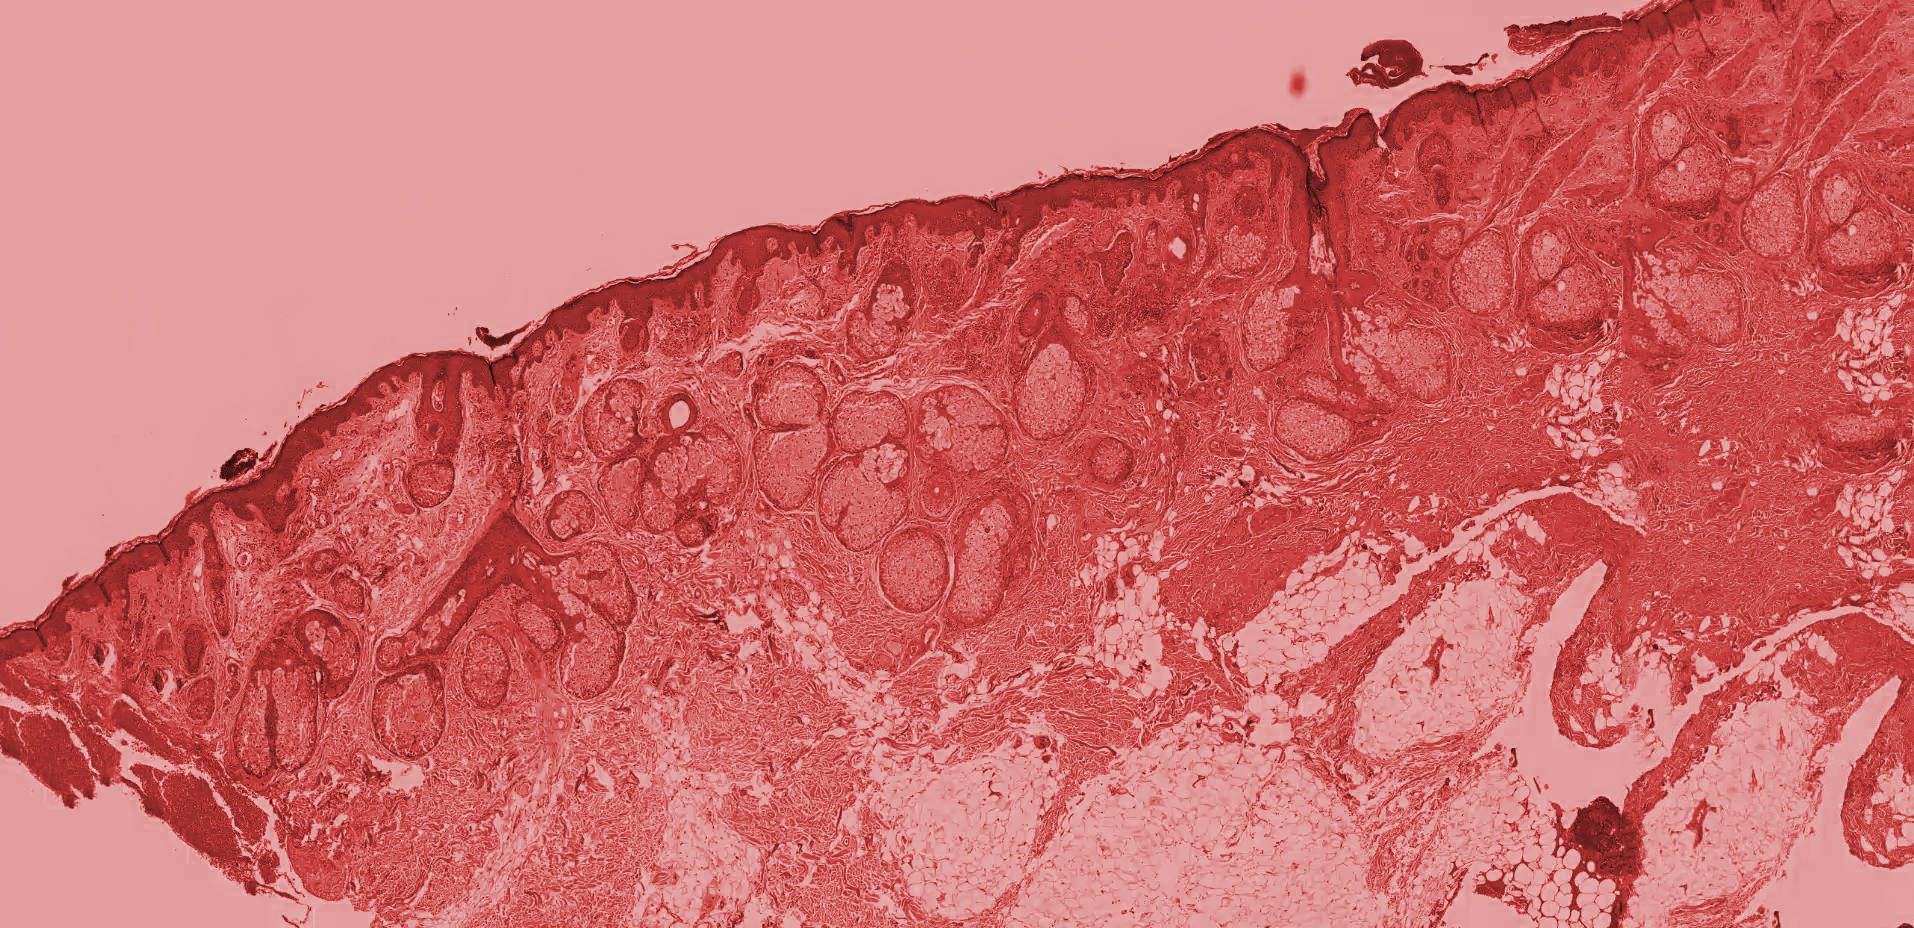

Histología

Se realiza el estudio anátomo-patológico de la biopsia para la detección o descarte de cualquier patología en el tejido.

Tipo de muestra: Biopsias gástricas y unidades de tejido no mayores a 1cm de diámetro enviadas para análisis anátomo patológico.